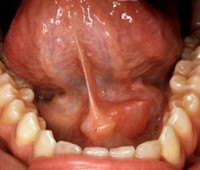

Постановка диагноза «острый сиаладенит» базируется на основе жалоб пациента, анамнеза заболевания, данных клинического осмотра, результатов дополнительных методов исследования. Во время физикального обследования пациента с острым эпидемическим сиаладенитом врач-стоматолог выявляет болезненную, чаще двухстороннюю припухлость тестообразной консистенции в проекции пораженных желез. Флюктуация отсутствует. При надавливании в участке угла нижней челюсти отмечается болезненность, что является одним из патогномоничных симптомов заболевания. При осмотре слизистой выявляют второй характерный признак острого эпидемического сиаладенита - гиперемию слизистой вокруг устья выводного протока железы.

При остром гриппозном сиаладените диагностируют наличие болезненной припухлости каменистой консистенции с бугристой поверхностью. Выделение слюны снижено. Рассасывание инфильтрата наблюдается в течение длительного отрезка времени. При остром бактериальном сиаладените из протока пораженной железы выделяется мутная слюна с примесью гноя. При развитии гнойной формы острого сиаладенита кожа над припухлостью становится гиперемированной, лоснится. Устье выводного протока возвышается над окружающей слизистой. Отмечается плотный резко болезненный инфильтрат. Присутствует перифокальный отек.